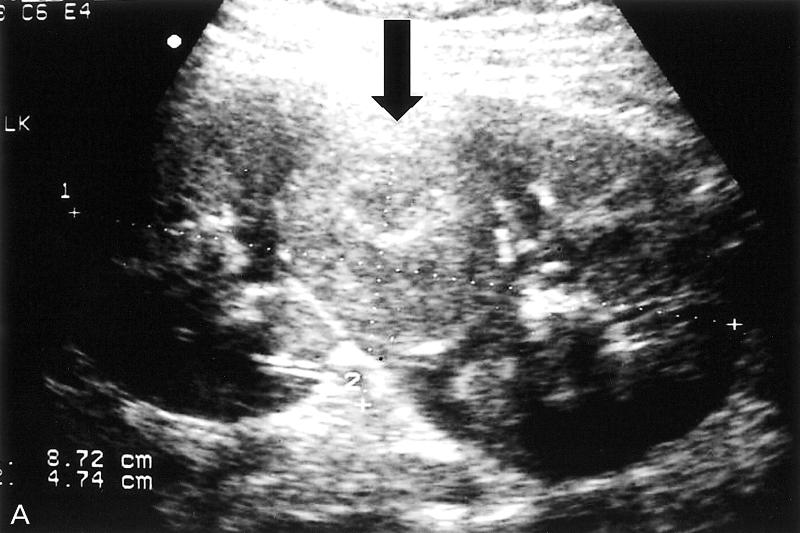

Most common solid renal mass in adults

hematuria

flank pain

palpable mass

lung mets

Renal Cell Carcinoma

Most common solid renal mass in adults

hematuria

flank pain

palpable mass

lung mets

Renal Cell Carcinoma